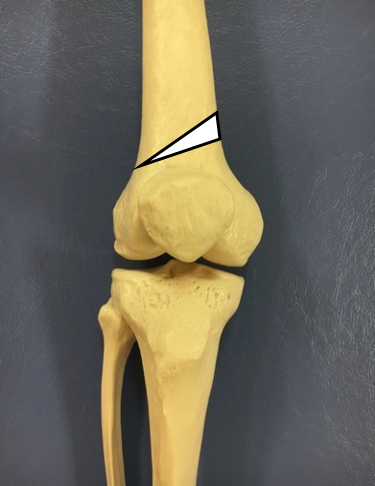

・大腿骨遠位骨切り術(DFO:Distal Femoral Osteotomy):(図2)

【図2 DFOの骨切り位置】

大腿骨と呼ばれるふとももの骨を膝に近い位置で切り、変形を矯正する手術になります。大腿骨を楔状に切り落として変形を矯正することがほとんどです。

一般的に、変形膝関節症による内反変形に対してはHTOまたはDTOが用いられ、外反変形に対してはDFOが用いられます(図5)。また、変形が高度の場合は、DLO(Double Level Osteotomy)と呼ばれる大腿骨と脛骨の両方の骨切りを行う手術も用いられます。